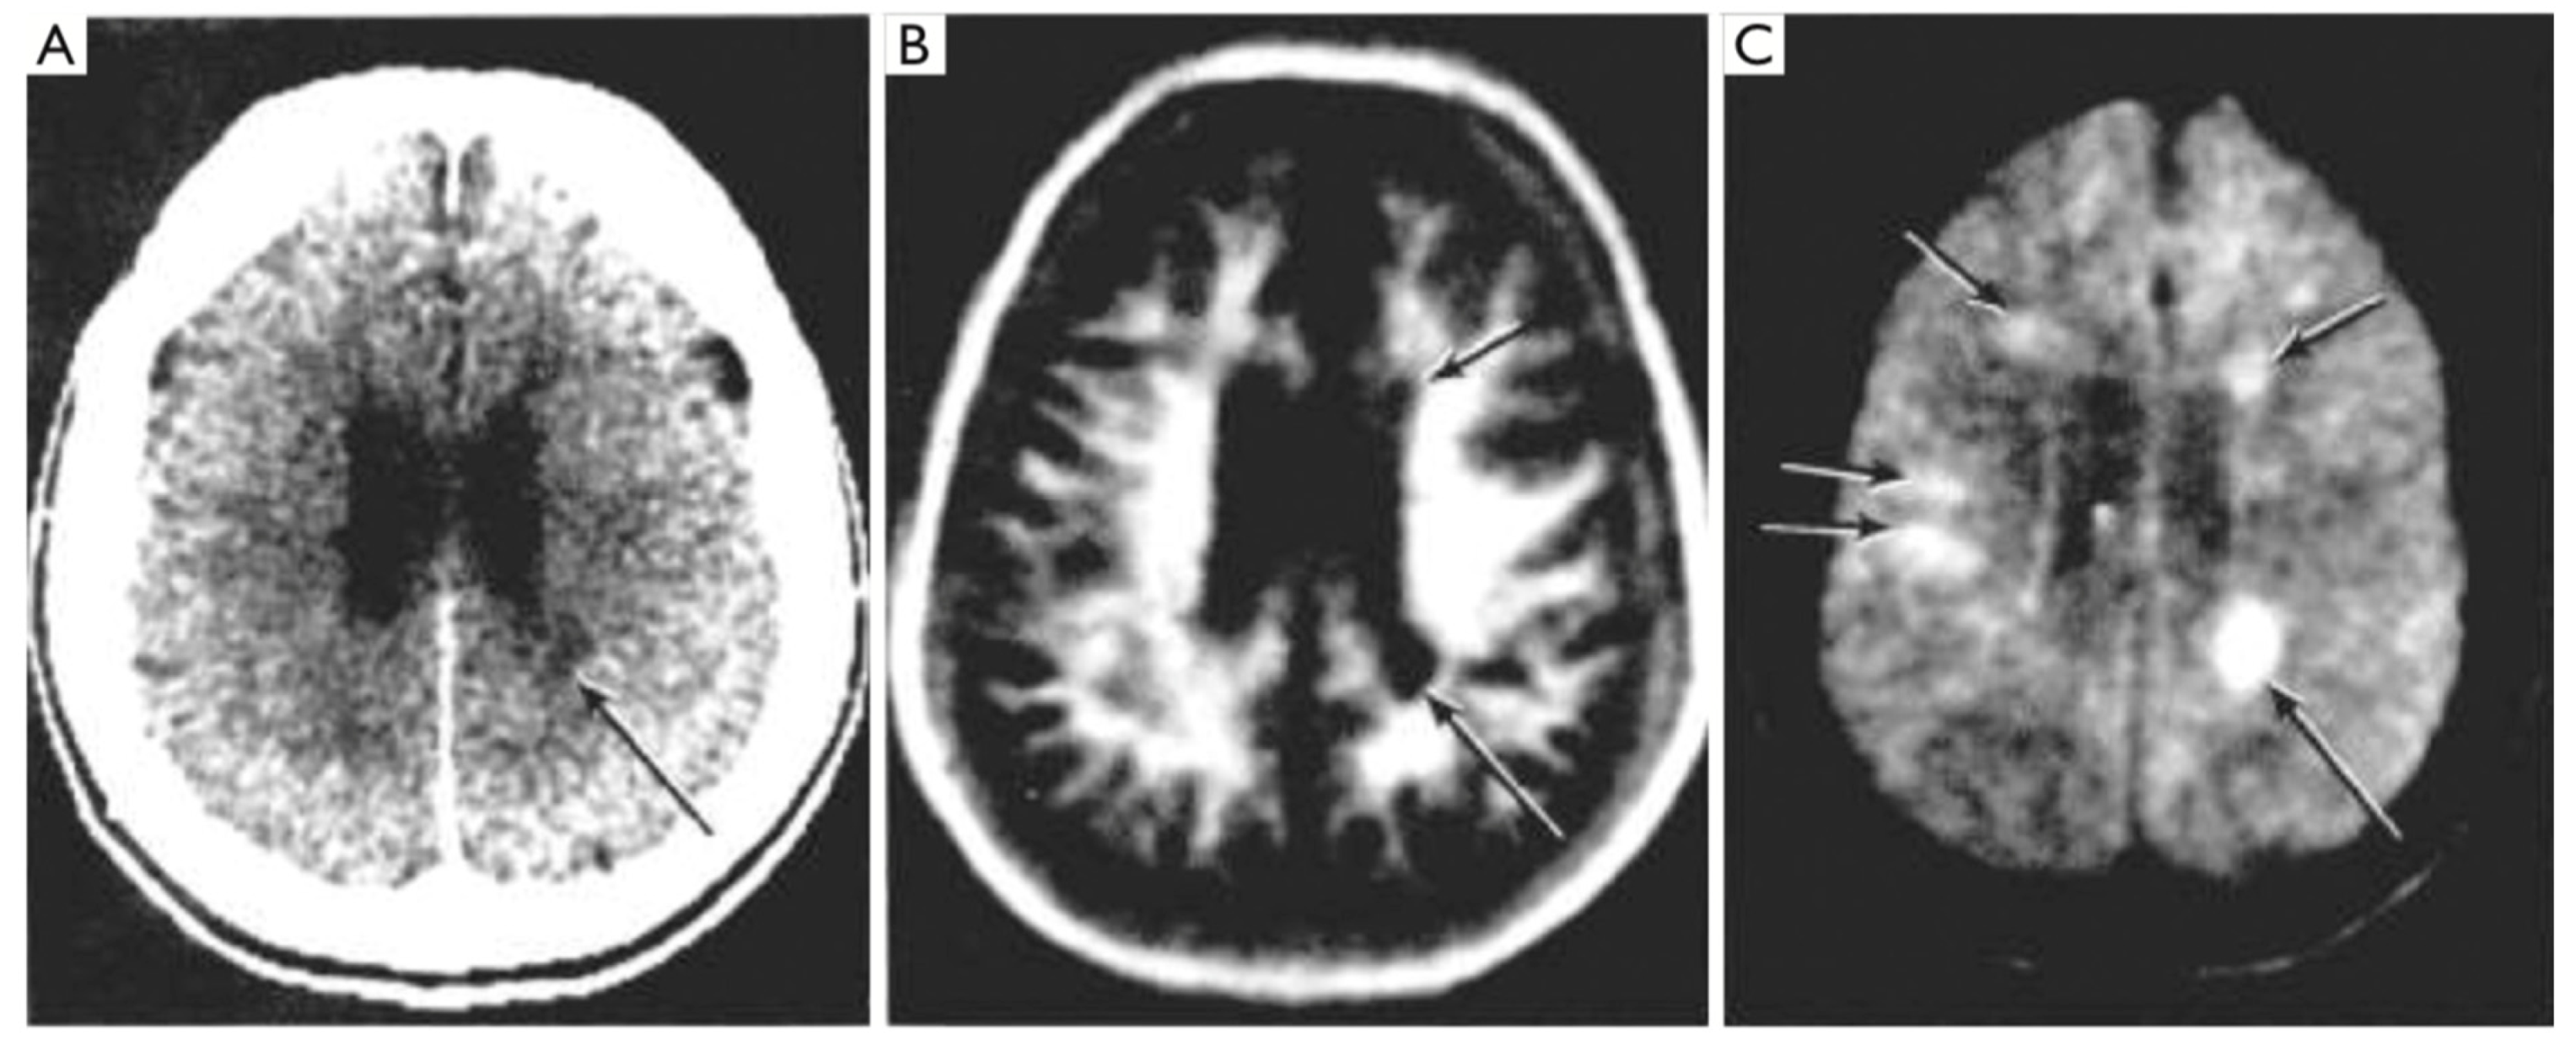

Figure 9.

CT (left) and STIR (right) images of a glioma (August 1985) [10]. Displacement of the falx is seen on the CT scan (left, black arrow) but there are no other abnormal features. The STIR image (right) shows very extensive high signal abnormalities in both cerebral hemispheres (open arrows). The high signal abnormalities on the STIR image are in normal appearing white matter on the CT image.